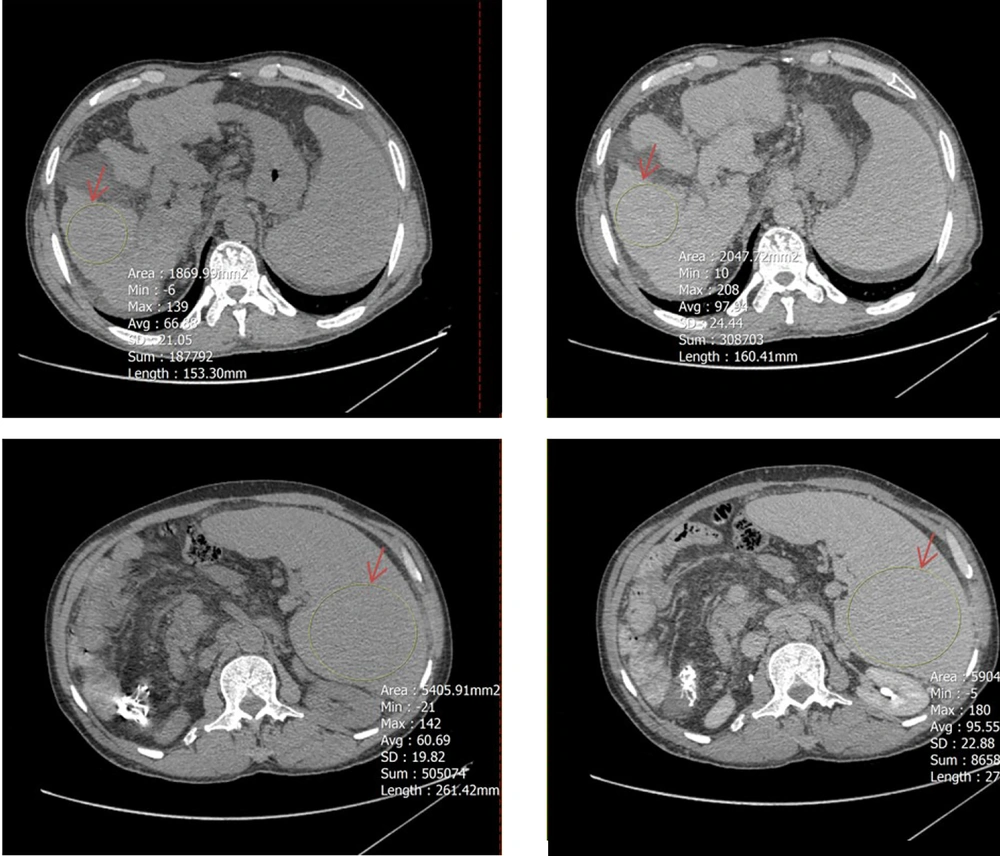

To determine mean Hounsfield units (HU) in both equilibrium and non-contrast phases, circular regions of interest (ROIs) were drawn as large as possible at specific anatomical landmarks. These included the right hepatic lobe at the level of the porta hepatis (Figure 2), the pancreas (head, body, and tail; averaged HU from the three segments was used to represent the whole organ) (Figure 3), and the spleen at its widest cross-sectional area, excluding vessels and focal lesions (Figure 2). An additional ROI with a 15-mm diameter was placed in the abdominal aorta at the level of the renal artery origin (Figure 4).

A circular region of interest (ROI, indicated by red arrows) was placed as large as possible on axial computed tomography (CT) images in both noncontrast (left) and equilibrium (right) phases. The upper panels show ROI placement in the right hepatic lobe at the level of the porta hepatis, while the lower panels demonstrate ROI positioning within the spleen at its maximum cross-sectional area, excluding visible vessels and focal lesions.